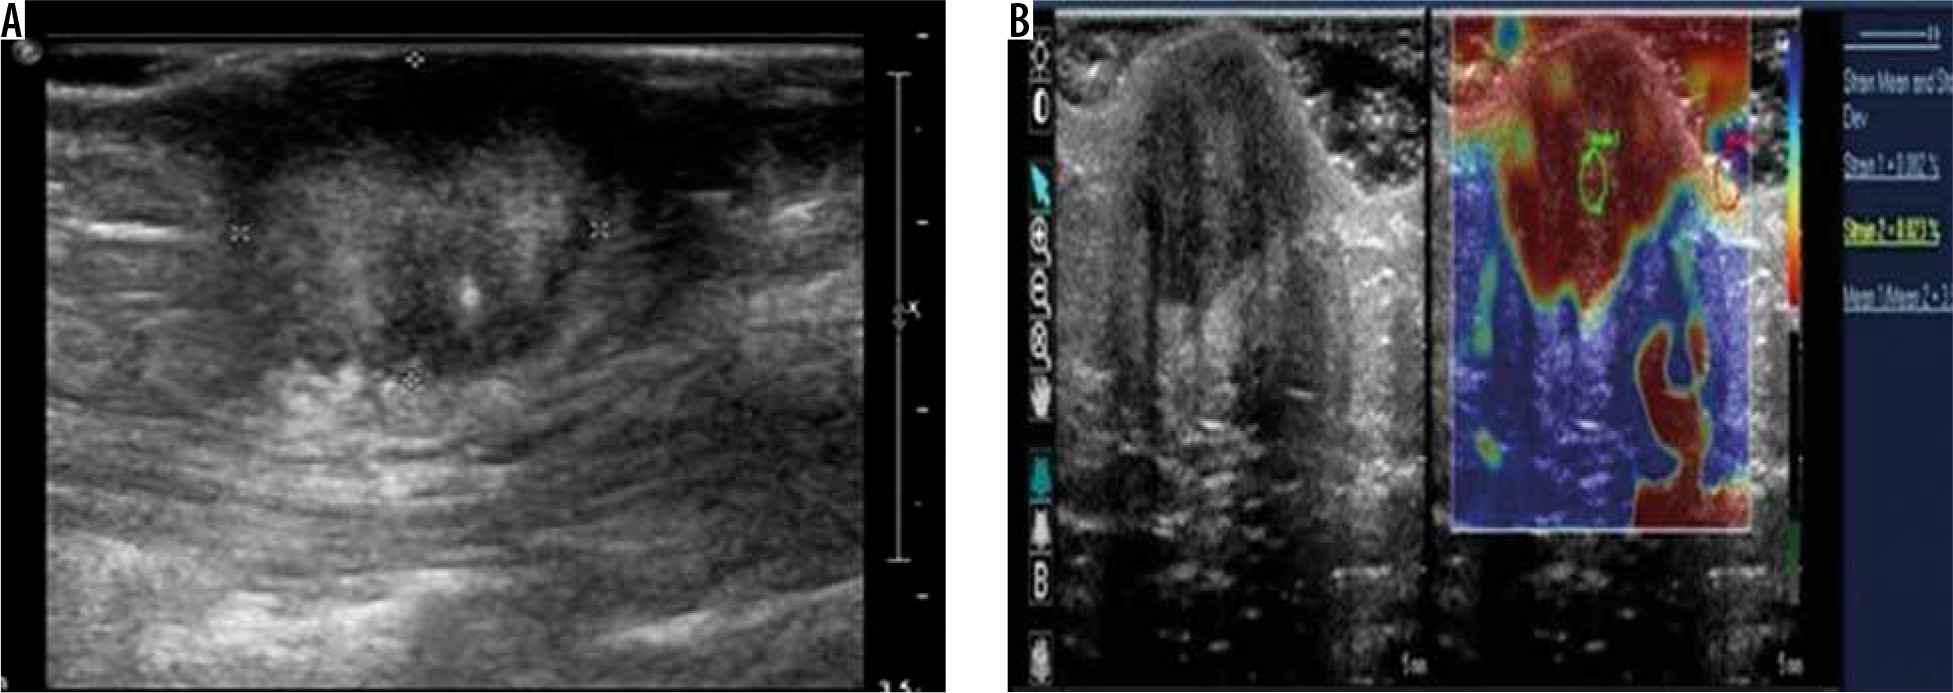

Figure 6

Epidermoid cyst – greyscale ultrasound image (A) shows a well-defined, predominantly hypoechoic lesion with posterior acoustic enhancement. Strain elastography assessment (B) of the same lesion depicts it predominantly in blue colour on elastography map and a strain ratio of 1.03 suggesting the “soft” nature of the lesion and a pointer towards a benign aetiology

The mean strain ratio in epidermoid cysts was 1.19 ± 0.08, which overlapped with that of lipomas (1.34 ± 0.45). The retrospective study by Park et al. found no significant differences between the strain elastography scores of epidermoid cysts and that of other benign tumours [13]. However, the epidermoid cysts were softer than the malignant superficial tumours. Although our study had limited number of cases, the single subcutaneous metastatic lesion we encountered had a strain ratio of 3.2 and that of fibroma and neurofibroma was higher than that of epidermoid cyst at 2.15 ± 0.92 and 2.85 ± 0.54, respectively. However, the significance of this could not be ascertained because it was a single case.